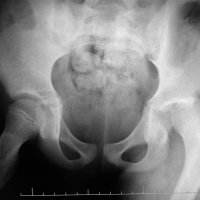

Pediatric traumatic hip dislocation are usually posterior and may occur due to low energy sports injuries in children less than 10 years of age. Hip dislocation are more common than hip fracture in pediatric patients and 80% are traumatic posterior dislocations.

Most of these cases can be diagnosed on AP pelvis films, which show loss of congruence of femoral head with acetabulum. Lateral view is sometimes is used to differentiate between anterior vs. posterior dislocation and to scrutinize femoral neck to rule out fracture prior to attempting closed reduction.

Treatment is urgent closed reduction under general anesthesia or sedation. Open reduction may be required if there is an intraarticular fragment following reduction. Post reduction imagings are necessary to inspect for joint incongruity or nonconcentric reduction.

MRI is a study of choice for any abnormal findings on post-reduction radiographs such as joint widening. In MR study, in inspect for joint incongruity or nonconcentric reduction. Entrapped labrum or capsule is best evaluated via MRI.

CT is second choice behind MRI for post-reduction evaluation, and also radiation exposure should be considered. Osteochondral fragments can be seen in older children and are easily detected by CT.

Delayed in reduction can lead to complications such as osteonecrosis, coxa magna, redislocation or nerve injury.